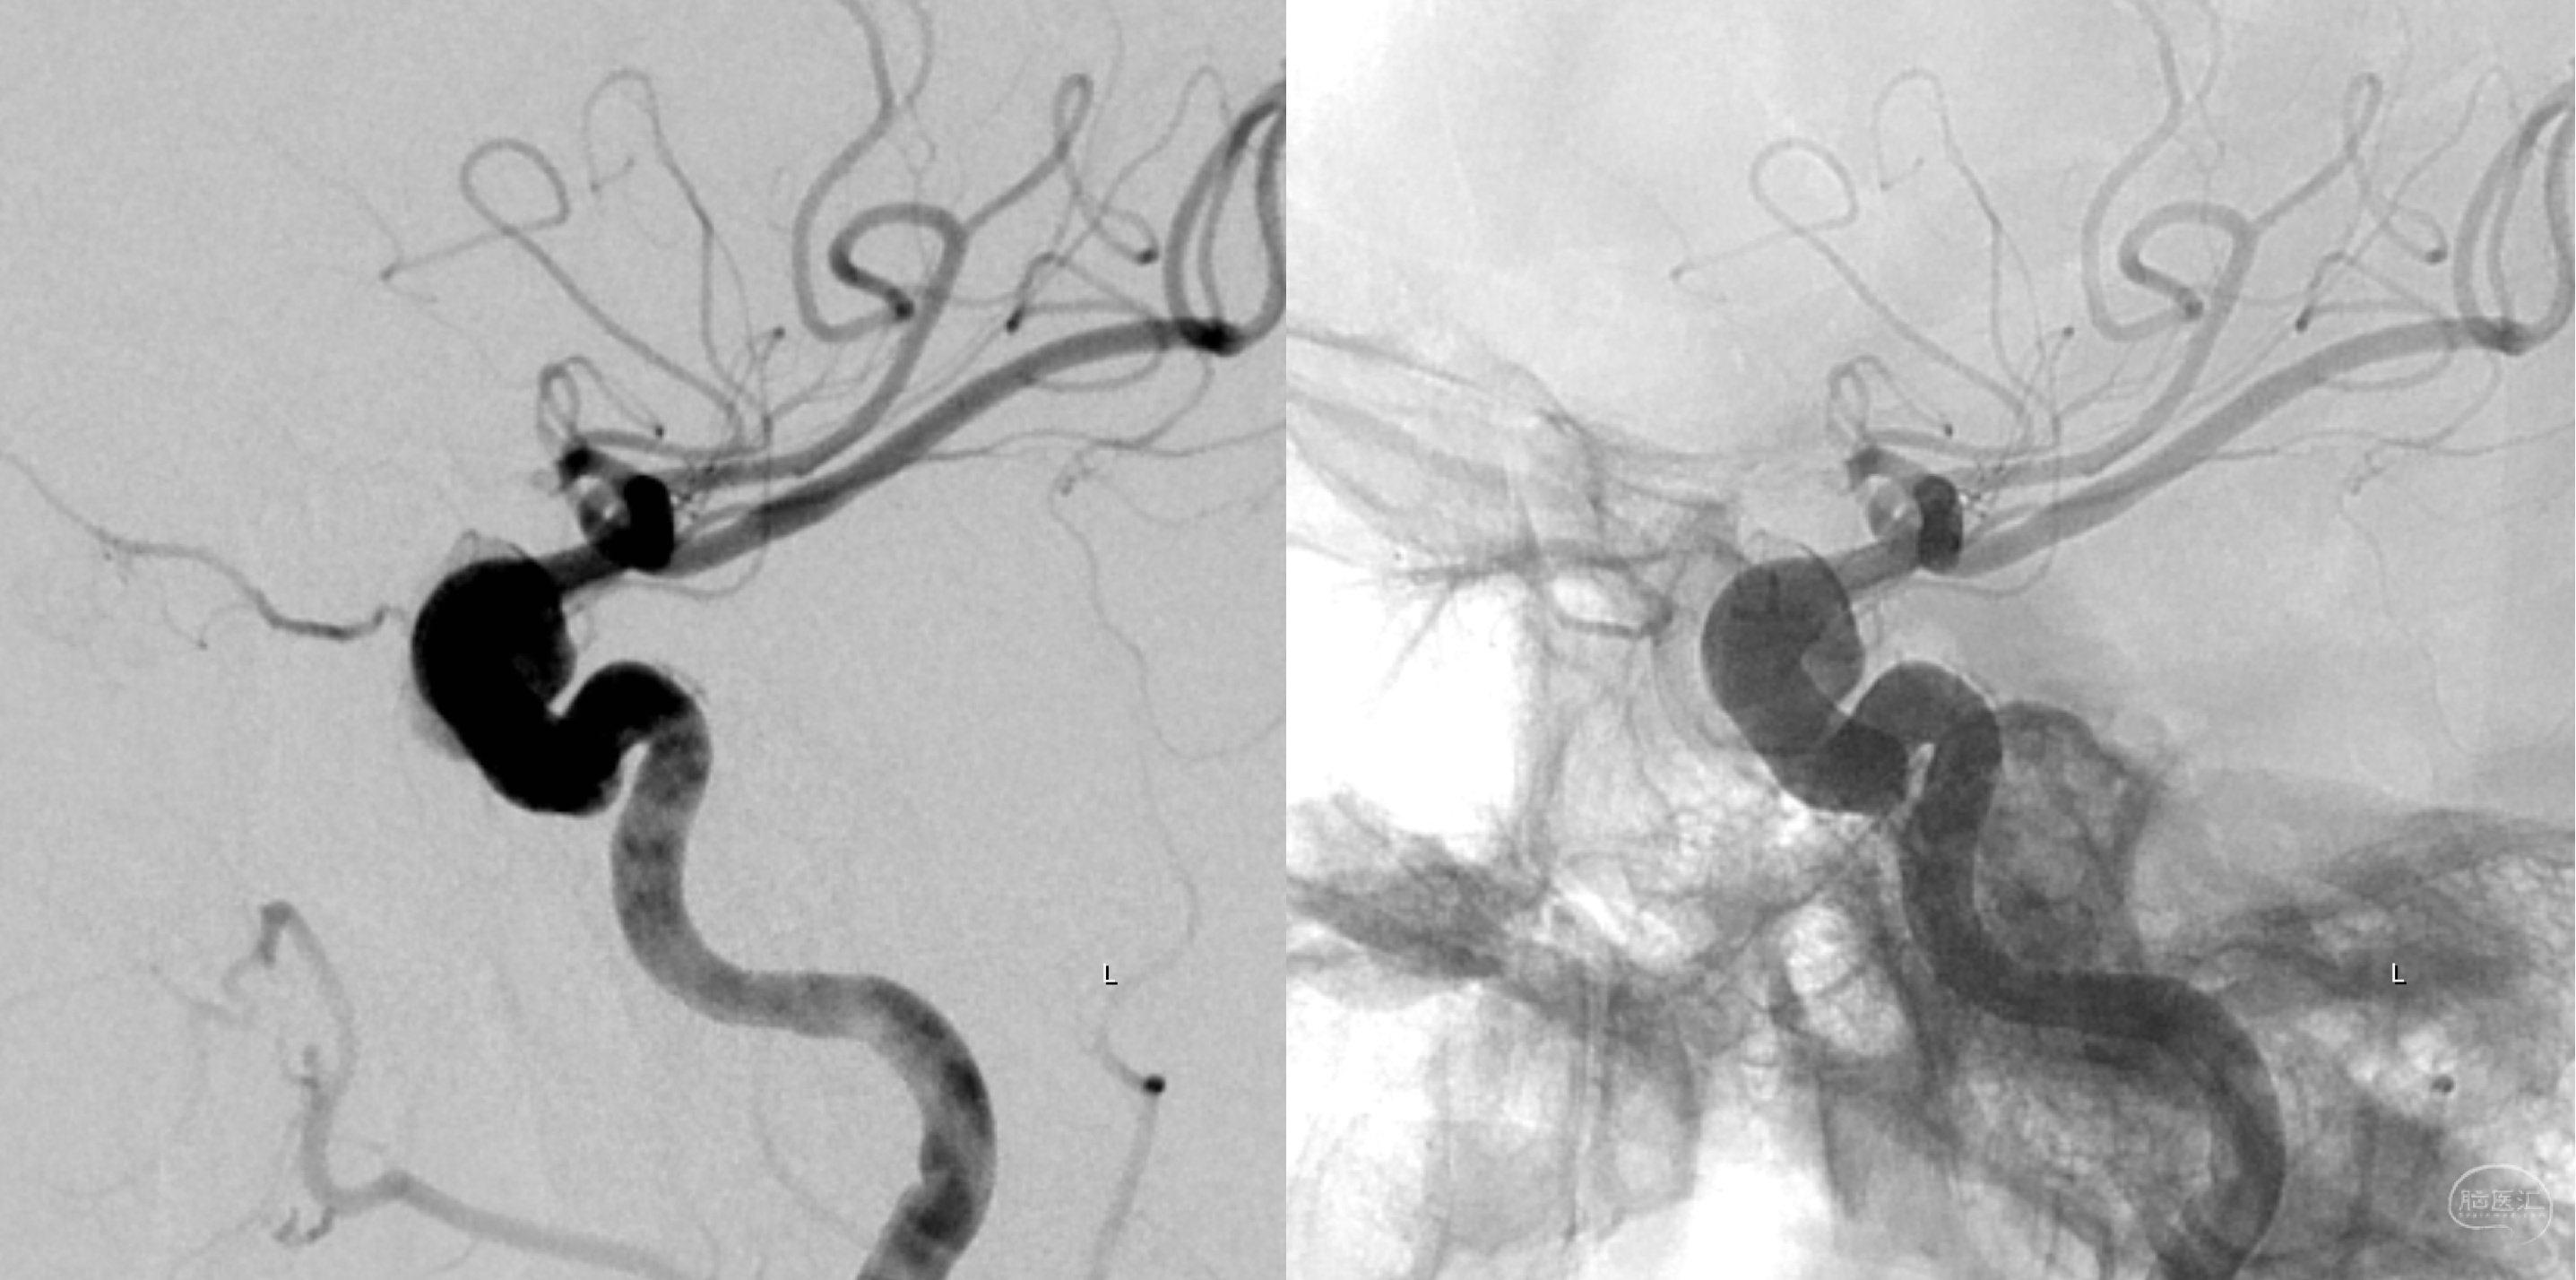

外院全脑血管造影:左侧颈内动脉眼动脉段动脉瘤。

外院左侧颈内动脉正侧位造影:眼动脉段动脉瘤。

外院左侧颈内动脉侧侧位造影:眼动脉段动脉瘤。

左侧颈内动脉正侧位造影:眼动脉段动脉瘤。

左侧颈内动脉三维重建:眼动脉段动脉瘤。

左侧颈内动脉三维重建:眼动脉段动脉瘤,海绵窦段血管略扩张。

术后工作位造影:动脉瘤内造影剂滞留明显!

术后正位造影及蒙片:动脉瘤内造影剂滞留明显,血管及支架形态良好!

术后正位造影及蒙片:动脉瘤内造影剂滞留明显,血管及支架形态良好!

术后侧位造影及蒙片:动脉瘤内造影剂滞留明显,血管及支架形态良好!